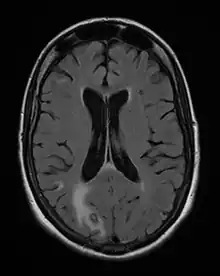

Les symptômes de début peuvent être insidieux, céphalées d'installation récente ou réactivation de céphalées anciennes, avec ou sans fièvre. Trois situations sont possibles :

- il s'agit d'un (ou de plusieurs) abcès cérébral (cas le plus fréquent) donnant un tableau neurologique rapidement progressif. Les signes cliniques dépendent de la localisation de(s) l'abcès : hémiplégie ou hémiparésie, syndrome cérebelleux, aphasie, amputation du champ visuel, ou signes plus diffus à type de somnolence, désorientation, crises comitiales ;